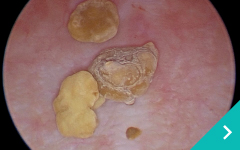

ミニマム創内視鏡下手術は腹腔鏡だけでは対処ができないような手術の際に、お腹にラッププロテクターという器具を設置して行う腹腔鏡と開腹手術を組み合わせた手術です。